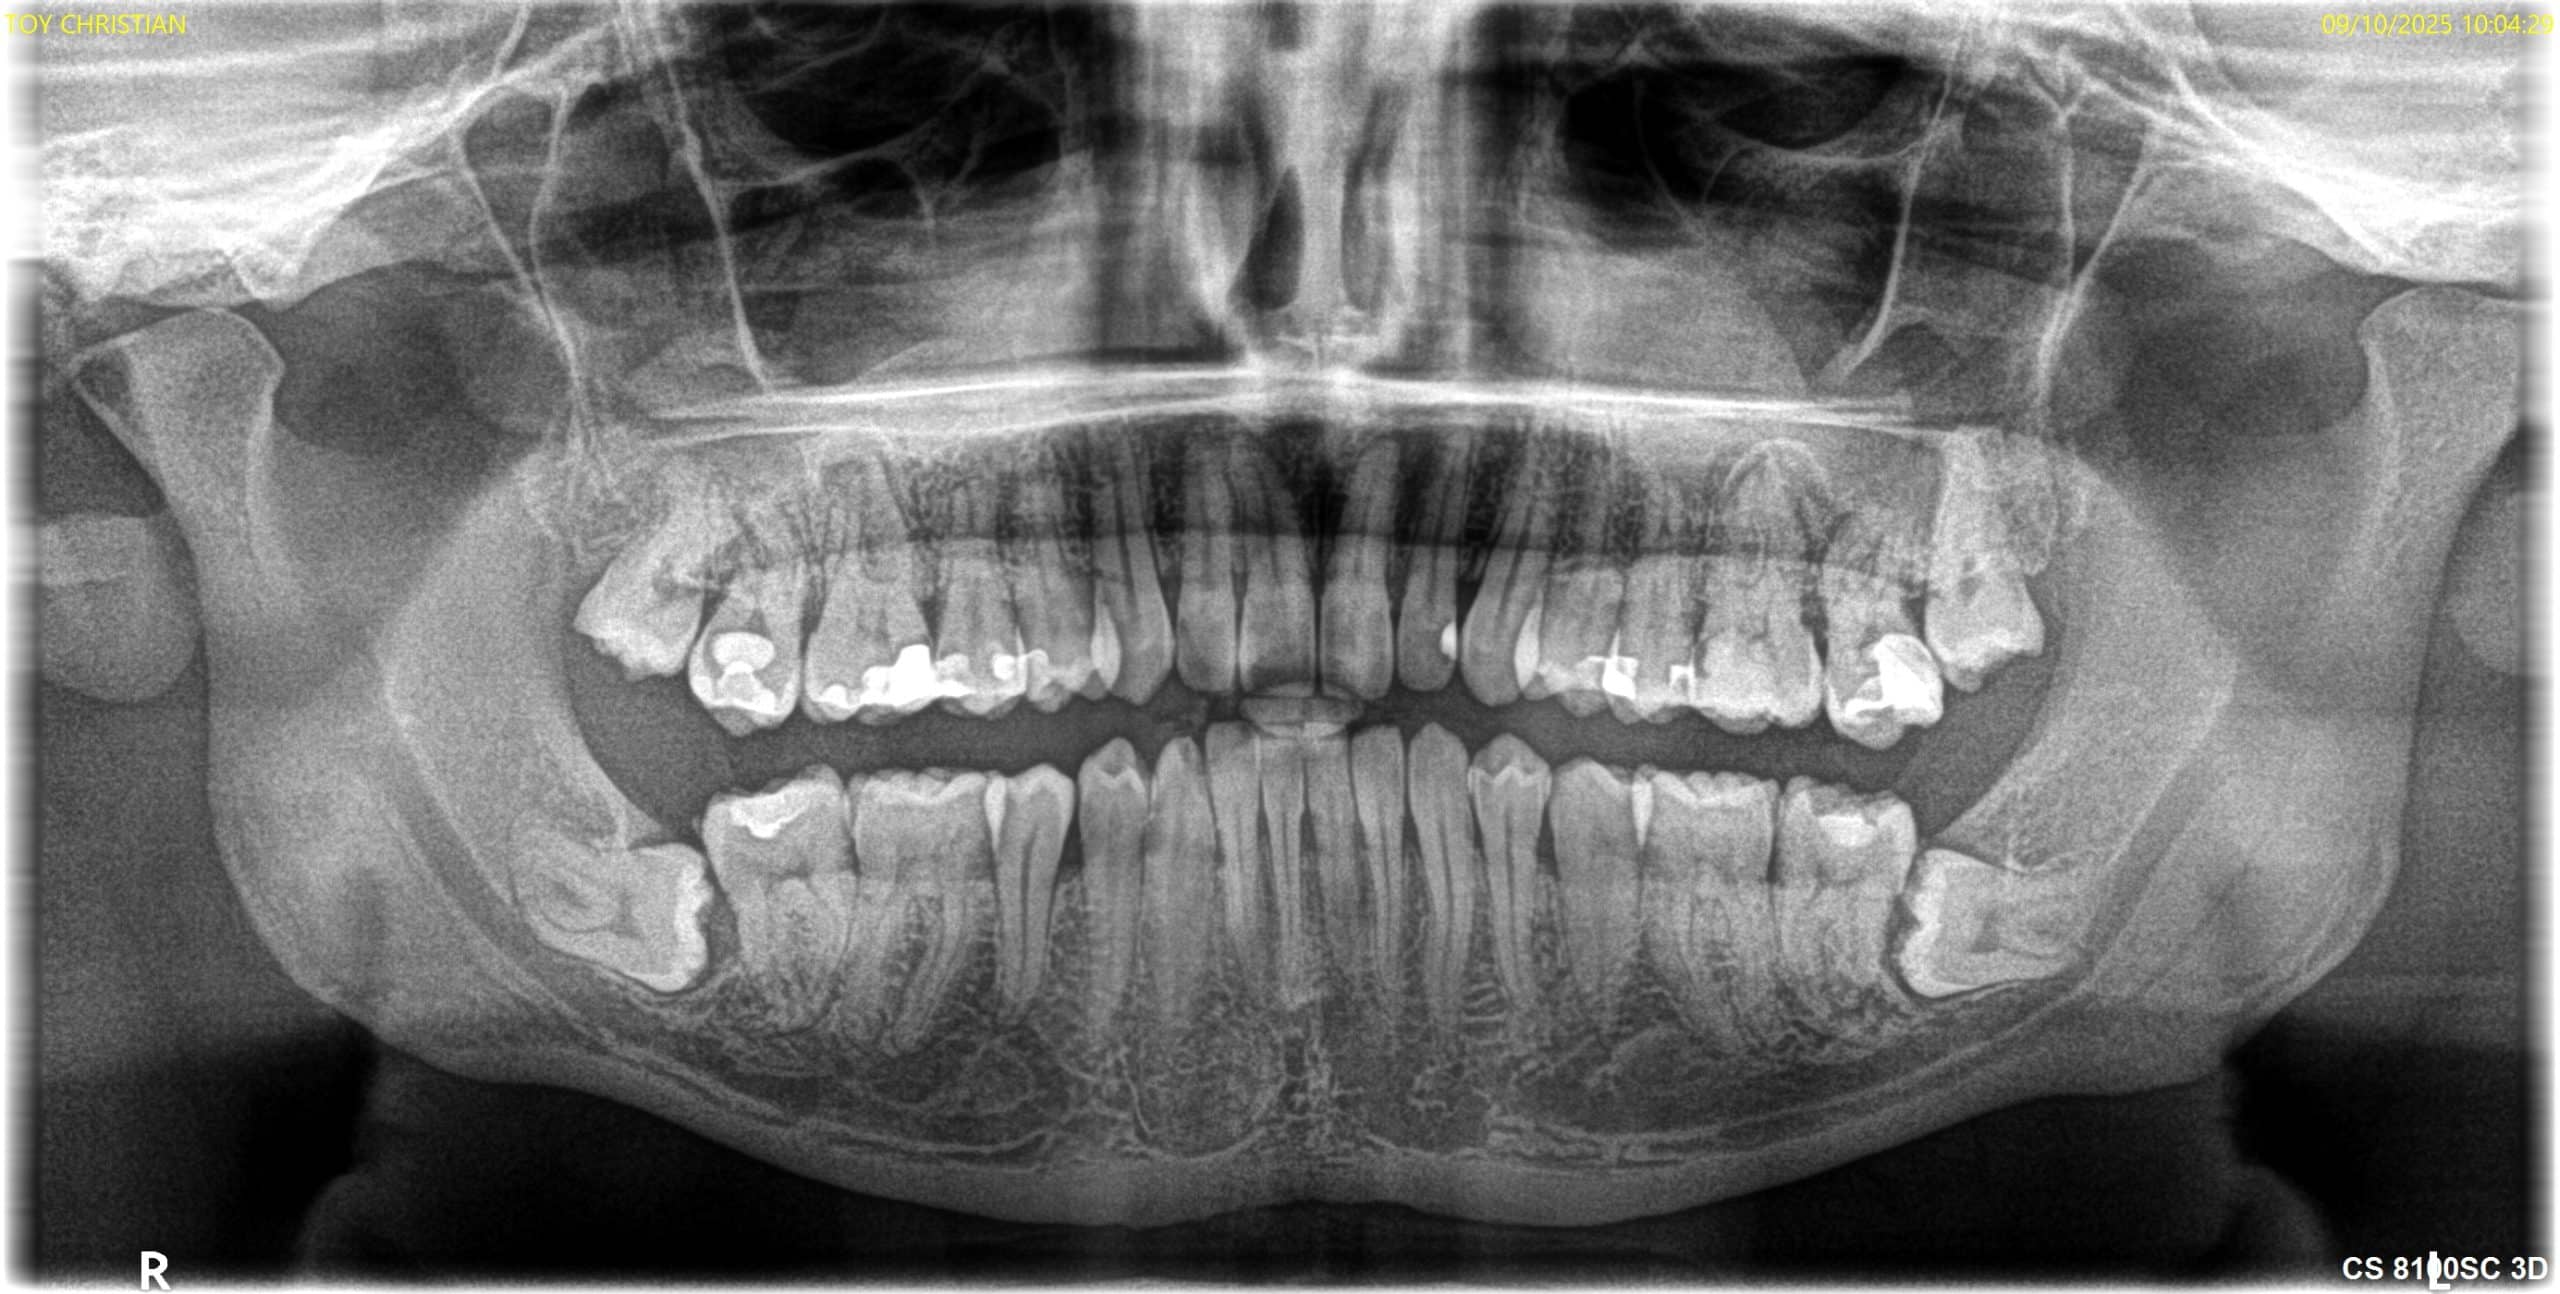

Tratamiento de endodoncia en piezas dentales con anatomía que presenta conductos accesorios de difícil acceso.

Paciente con presencia de caries extensas, se realiza tratamiento de conductos en 45-46 y posterior restauración con coronas cerámicas.

Paciente con dolor agudo tras obturación extensa en pieza 2.6. Se realiza tratamiento de conductos i restauración bajo anestesia en una sola sesión.